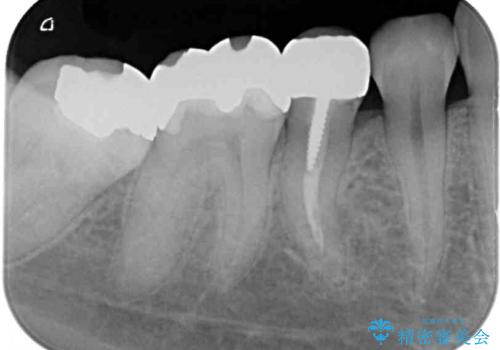

レントゲン写真から、以前治療した詰め物の下に虫歯があることがわかりました。

精度が高く、虫歯の再発リスクの低いゴールドインレーで治療を行うこととしました。